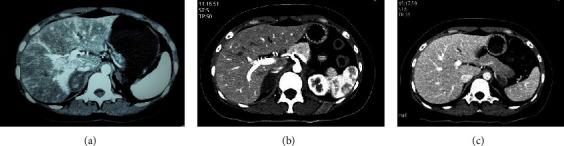

Antiphospholipid syndrome (APS) is an autoimmune disorder while adrenal hemorrhage could be its rare complication. Herein, we report the case of a 32-year-old unmarried woman with a history of systemic lupus erythematosus (SLE) who was hospitalized after complaints of upper abdominal pain, limb weakness, and loss of appetite for 2 weeks. Laboratory examination revealed hyponatremia, low plasma cortisol levels, increased adrenocorticotropic hormone levels, and a positive anticardiolipin antibody status. Furthermore, computed tomography (CT) revealed the presence of bilateral adrenal masses. Ultimately, based on dynamic changes in CT images, these masses were diagnosed as adrenal hemorrhage owing to APS. A computer-assisted literature search was conducted to identify cases of primary adrenal insufficiency associated with APS and/or SLE. The clinical features, laboratory examination, treatments, and outcomes of these cases were summarized. Our findings emphasize the importance of screening for adrenal insufficiency in patients with SLE or APS who present with abdominal complaints, asthenia, and hyponatremia. It is also recommended to test for APS all patients with adrenal hemorrhage.

抗磷脂综合征(APS)是一种自身免疫性疾病,而肾上腺出血是其罕见的并发症。在此,我们报告一例32岁未婚女性,有系统性红斑狼疮(SLE)病史,因上腹部疼痛、肢体无力和食欲不振2周后入院。实验室检查显示低钠血症、血浆皮质醇水平降低、促肾上腺皮质激素水平升高以及抗心磷脂抗体阳性。此外,计算机断层扫描(CT)显示双侧肾上腺肿块。最终,根据CT图像的动态变化,这些肿块被诊断为APS所致的肾上腺出血。通过计算机辅助文献检索,确定与APS和/或SLE相关的原发性肾上腺功能不全病例。总结了这些病例的临床特征、实验室检查、治疗方法和结果。我们的研究结果强调了对出现腹部不适、乏力和低钠血症的SLE或APS患者进行肾上腺功能不全筛查的重要性。还建议对所有肾上腺出血患者进行APS检测。